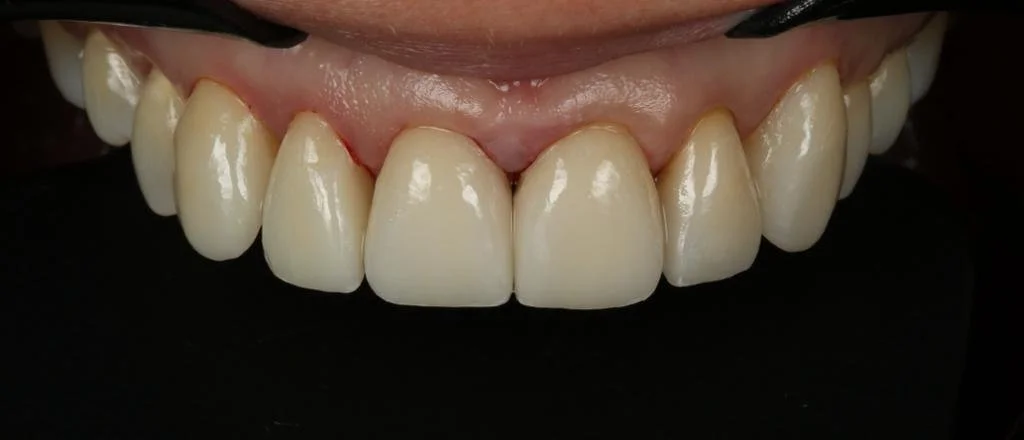

Cerec Reshape and Stain Graze